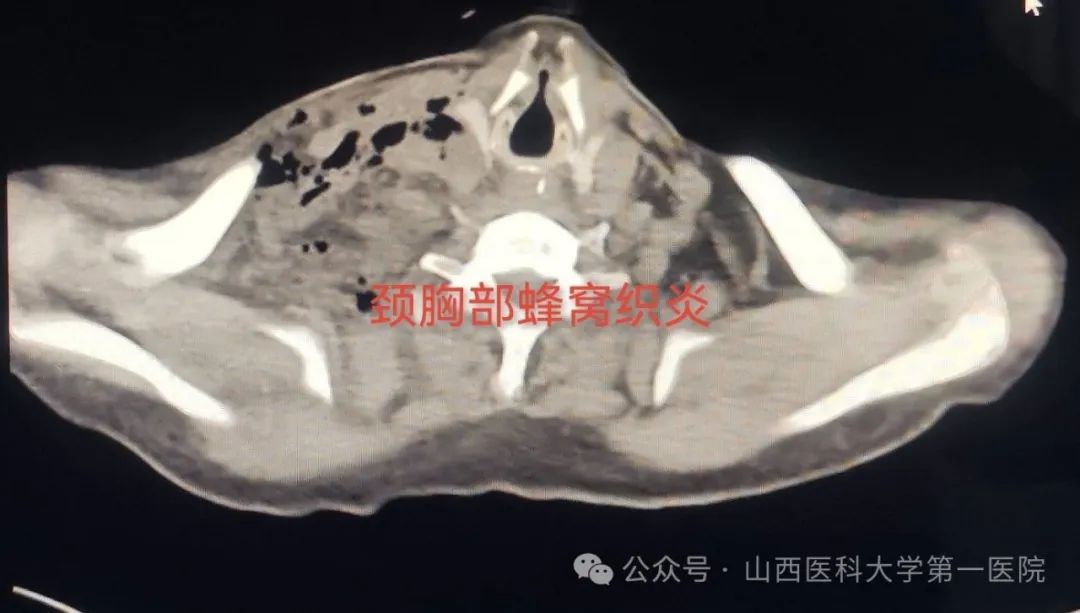

认为病情危重建议转入山医大一院。入院后,耳鼻咽喉-头颈外科医生完善各项辅助检查,积极给予消炎消肿抗感染药物治疗,但是颈部肿胀逐渐明显,患者一侧颈部已有大面积红肿、膨隆,皮肤出现捻发音,颈部超声检查及颈部CT检查提示:颈部严重感染,脓肿形成,纵隔感染,脓胸。若不及时处置很有可能造成败血症、脓毒血症,引发感染性休克而危及生命。

据皇甫辉教授介绍,患者所患为颈部蜂窝组织炎,而急性蜂窝组织炎是皮下、筋膜下、肌间隙或深部蜂窝组织的急性弥漫性化脓性感染,致病菌有溶血性链球菌、金黄色葡萄球菌和厌氧菌,溶血性链球菌导致急性蜂窝组织炎由于链激酶和透明质酸酶作用病变扩展迅速,可以引起败血症;患者由于高龄、心肺功能差、抵抗力差,蜂窝组织炎如果不及时处理极有可能造成生命危险,若感染炎症向下蔓延播散,引起咽喉部急性炎症、咽喉脓肿,可发生上呼吸道阻塞并迅速出现呼吸困难;如炎症扩散经咽侧壁侵入咽旁隙,则形成咽旁间隙脓肿,少数患者可并发颈动脉鞘感染、颈静脉血栓、脓毒血症、化脓性颈淋巴结炎等严重并发症发生。

尽管患者高龄,食管穿孔后并发颈部蜂窝组织炎,出现颈部脓肿、纵隔脓肿、脓胸、脓毒血症、肺部感染、心律失常、房颤、肺动脉高压、左右心房扩大、低蛋白血症、水电解质与酸碱平衡紊乱、下肢静脉血栓形成、真菌感染、耐药菌株产生等危重情况,医护人员克服一切困难,及时调整医疗与护理方案,消炎消肿抗感染、颈部切开引流、胸腔闭式引流等,矫正水、电解质紊乱与酸碱紊乱,对症治疗等,经过两个多月的精心呵护,患者最终痊愈出院。